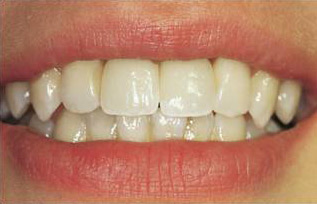

poslije